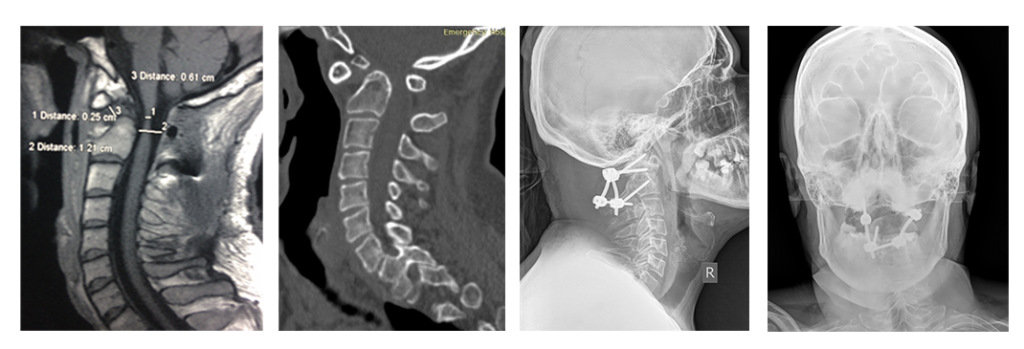

На снимках: ребенок 3 лет со спондилоэпиметафизарной дисплазией и тетрапрегией, имеется нестабильность в области краниоцервикального перехода с сдавлением спинного мозга. Стрелкой обозначен смещенный вперед атлант. Очень маленькие размеры позвонков. Проведена фиксация «второй шейный позвонок – затылок», костная пластика. Смещение атланта и нестабильность устранены. Восстановление движений в конечностях после операции. Ребенок самостоятельно начал ходить.

На снимках: пациент 36 лет с атланто-аксиальной нестабильностью и сдавлением спинного мозга на фоне врожденного порока развития «зубовидной кости» (обозначена стрелкой). Тетрапарез после незначительной травмы. Проведена передняя мобилизация для устранения смещения и задняя фиксация с устранением нестабильности, костная пластика.